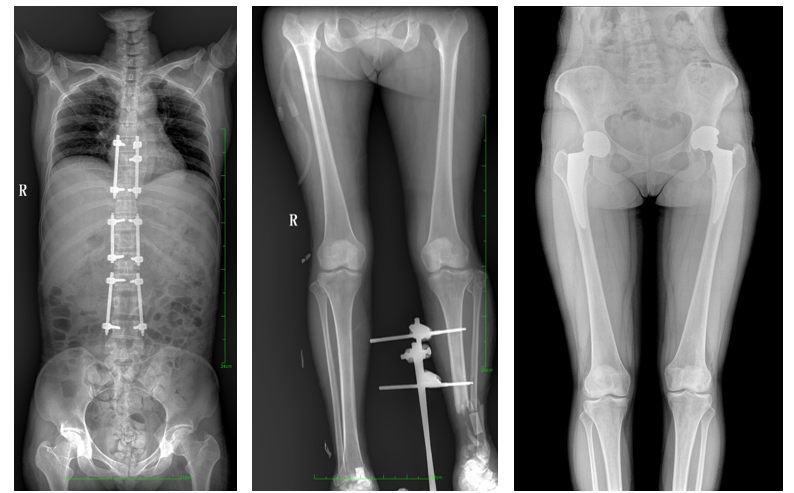

一、成像面積大。17"*34"有效視野,一次成像不拼接。相較于多張攝影再軟件拼接的DR設(shè)備,PLX8600解決了拼接圖像存在密度不均勻,拼接處圖像配準(zhǔn)和放大效應(yīng)等問題,給臨床帶來了大視野影像解決方案,可一次性覆蓋全脊柱或雙下肢影像。

PLX8600大視野平板動態(tài)DR攝影速度快,患者可以更快地完成檢查,且單次攝影輻射劑量是常規(guī)多張攝影再軟件拼接DR的1/2或1/3,低劑量給患者更多關(guān)愛。

PLX8600大視野平板動態(tài)DR可在低輻射劑量下獲得患者站立位、臥位的高質(zhì)量影像。搭載自主研發(fā)的圖像均衡處理系統(tǒng),能夠很好的均衡人體不同厚度組織的影像,視野大,圖像清晰,層次豐富。如果您想采購這款產(chǎn)品,歡迎聯(lián)系我們,咨詢電話400-025-6366。